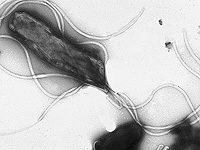

Wikipedia.org. Фото: Yutaka Tsutsumi, M.D. Professor Department of Pathology Fujita Health University School of Medicine

Ранее считалось, что язвы желудка возникают из-за острой пищи или неправильного питания. Однако современные исследования показали, что основной причиной большинства язв и повышенного риска рака желудка является бактерия Helicobacter pylori, которой заражены более 60% населения мира. Сегодня ученые биологического факультета Школы естественных наук и инженерии Университета Атенео де Манила разрабатывают вакцину против этой бактерии, которая потенциально может предотвратить язву желудка и снизить риск рака этого органа.